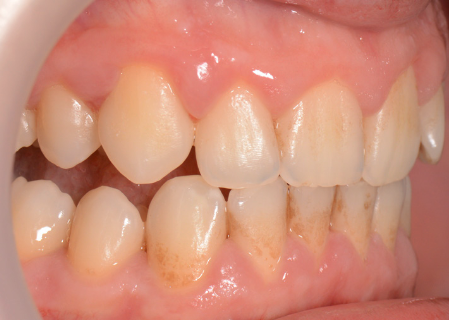

Mulți pacienți tind să amâne vizita la medic, pentru că de cele mai multe ori nu este prezentă senzația dureroasă. Placa bacteriană greu accesibilă și mai ales tartrul pot fi îndepărtate printr-un simplu detartraj cu ultrasunete și un periaj dentar profesional efectuate o dată la 6 luni de către medicul dentist. Spațiile mai greu accesibile cu tartru aderent se vor igieniza mecanic cu instrumente speciale de detartraj: chiurete parodontale și scalare. Prin îndepărtarea plăcii bacteriene și a tartrului și prin menținerea unei igiene corecte, semnele de afectare gingivală vor dispărea, iar gingia își va recăpăta starea de sănătate inițială. Gingivita simplă netratată va evolua în anumite zone ale cavității orale spre boala parodontală. Netratată, aceasta se va extinde treptat la tot mai mulți dinți, având o evoluție cronică și într-un final, după distrucții extinse, se vor pierde dinții. Tratamentul bolii parodontale este mult mai complicat și mai laborios decât al unei gingivite simple, de aceea este foarte important să se intervină în stadii cât mai incipiente ale bolii. (Fig. 5.1.5, 5.1.6, 5.1.7)